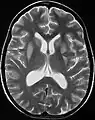

El antecedente de haber sufrido hiponatremia, sumado a las características clínicas previamente descritas son el sello de la enfermedad. La resonancia magnética puede mostrar ciertos cambios a nivel del parénquima cerebral, como es el aumento en la intensidad a nivel pontina[4]

Mielinolisis central pontina

Resonancia que muestra aumento de la intensidad de la imagen bilateral y simétrica a nivel del caudado (flecha pequeña), putamen (flecha larga) con extensión hasta el globo pálido, sugerente de mielonisisi extrapontina